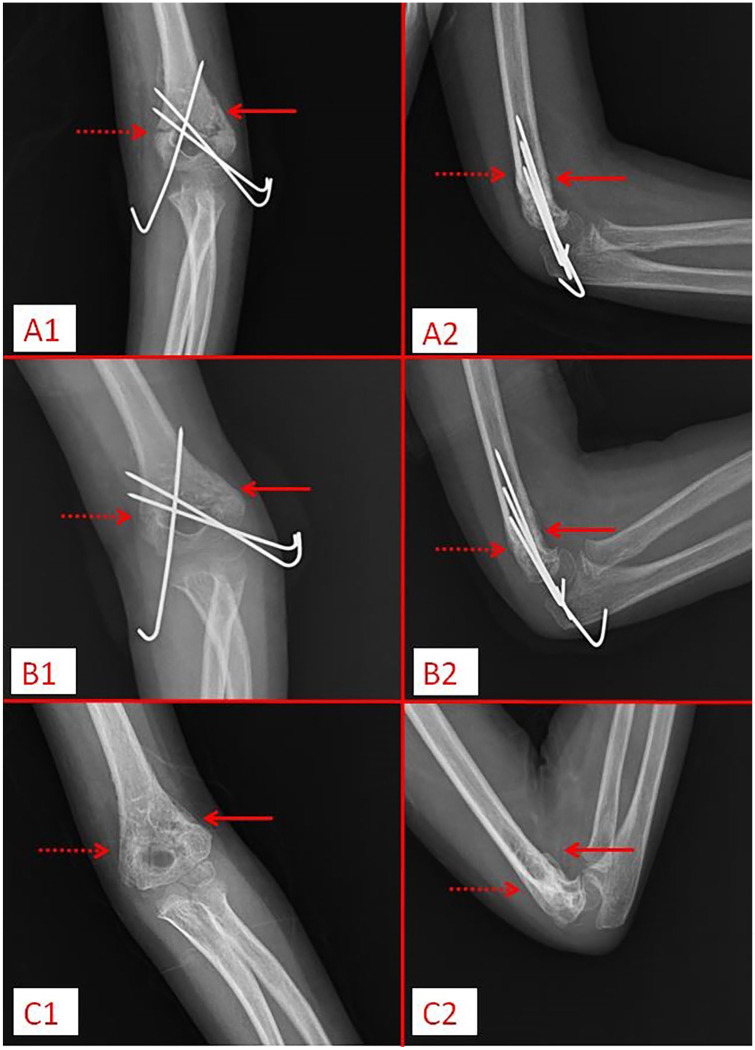

Methods: In this prospective study, patients who were operated on for supracondylar humerus fractures were called for follow-up three times: postoperative splint removal, pin removal, and final control. A total of 58 patients, 34 boys and 24 girls, who provided regular follow-ups, were included in the study. During follow-ups, the Radiographic Union Score for Tibial Fracture was calculated by evaluating the patients' elbow anteroposterior and lateral radiographs, and the elbow joint range of motion was recorded with a goniometer. In two experiments, orthopedic surgeons evaluated intraobserver and interobserver reliability using the intraclass correlation coefficient at different times. The patients were evaluated at the last follow-up according to the Flynn criteria.

Results: The first follow-up Radiographic Union Score for Tibial Fracture (median (range) was 8 (7-10), the second follow-up was 11 (9-12), and the third follow-up was 12 (11-12). Range of motion was 40° at the first follow-up, 90° at the second follow-up, and 120° at the third follow-up. Radiographic Union Score for Tibial Fracture and range of motion increased significantly as the weeks progressed (p < 0.001). Interobserver intraclass correlation coefficient at first follow-up was 0.80 (95% confidence interval 0.69-0.87), second follow-up was 0.85 (0.77-0.91), and third follow-up was 0.79 (0.67-0.87). Intraobserver intraclass correlation coefficient was 0.92 (0.88-0.95) at the first follow-up, 0.93 (0.98-0.96) at the second follow-up, and 1.00 (1.00-1.00) at the third follow-up. Flynn score results are functional; the cosmetic results were excellent in 46 patients, good in 4 patients, fair in 5 patients, poor in 3 patients, and cosmetic results were excellent in 54 patients and good in 4 patients.